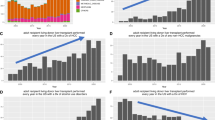

Outcomes of Small Grafts with the Utilization of Inflow Modification

In order to minimize the risk of the donor, efforts have been made to enhance the utilization of left lobe grafts. However, the caveat associated is the increasing possibility of inducing small for size syndrome (SFSS) shifting the risk to the recipient [21•].

Despite the fact it is well established, the risk of SFSS is increased when the graft weight/recipient weight (GW/RW) ratio is <0.8 % or the graft weight/standard liver volume (GW/SLV) ratio is <40 %; various reports support the use of smaller grafts with excellent patient and graft survival. These reports sustain the cause of SFSS is multifactorial including the size of the donor graft, degree of portal hypertension and general condition of the recipient manifested by the MELD score; suggesting, therefore, a key component of successful outcome requires careful recipient selection and implementation of IM if needed [25–28].

Soejima et al. [27] compared the outcome of living donor liver transplantation using left and right lobe grafts. The authors concluded that left lobe grafts should be considered as much as possible for donor safety; however, they should not be used in recipients with MELD score >30 if GW/SVL is <35 %. Additionally the implementation of splenectomy alone or in combination with hemiportocaval shunt was critical when using extra-small grafts. In line with this, Hill et al. [29] compared outcomes between recipients undergoing transplantation with GW/RW ratio <0.8 % (average MELD 15.7) and ≥0.8 % (average MELD 17.7) with similar results. In another study, Troisi et al. [26] compared recipients receiving small grafts with GW/RW ratio ≤0.8 % with and without IM via hemiportocaval shunt. The utilization of IM improved 1 year patient and graft survival from 40 % to 87.5 % and from 20 % to 75 %, respectively. Botha et al. [28] reported 21 left lobe adult LDLTs with IM via hemiportocaval shunt in 16 patients with a median GW/RW ratio of 0.67 % reducing the median portocaval gradient from 18 to 5 mmHg. Ogura et al. [23] reported the use of splenectomy alone or in combination with meso-renal shunt to keep the portal pressure after reperfusion under 15 mmHg. This increased the utilization of small grafts (GW/RW <0.8 %) from 7.8 to 23.9 % and the utilization of left lobes from 4.9 to 32.1 %.

Despite the evidence of the advantage of IM in optimizing the utilization of small grafts and specifically left lobe grafts, there are other factors—as previously mentioned—that contribute to SFSS in addition to portal hyper perfusion/pressure. An example of this is reflected in the study by Ishizaki et al. [30] where in 24 of 42 left lobe adult LDLTs, the GW/SVL was <40 % and in 17 cases the GW/RW ratio was <0.8 %. The mean portal pressure after reperfusion was 21.5 ± 3.6 mmHg and no IM was implemented. There were no SFSS and patient and graft survivals were 100, 97 and 91 % at 1, 3 and 5 years respectively.

Additionally, since usually the volume provided by a left lobe graft is <40 % of the total liver volume, efforts to include the caudate lobe with the left graft should be considered since this can increase the graft volume up to 9 % in most cases [31].

In summary, when selecting small grafts balancing the risk between the donor and recipient should consider both donor and recipient variables. These should include the graft size, donor age, recipient overall condition including MELD score and level of portal hypertension. Under these considerations and with the implementation of IM, it is possible to enhance the utilization of the left lobe improving the donor safety and preserving the recipient’s outcome.